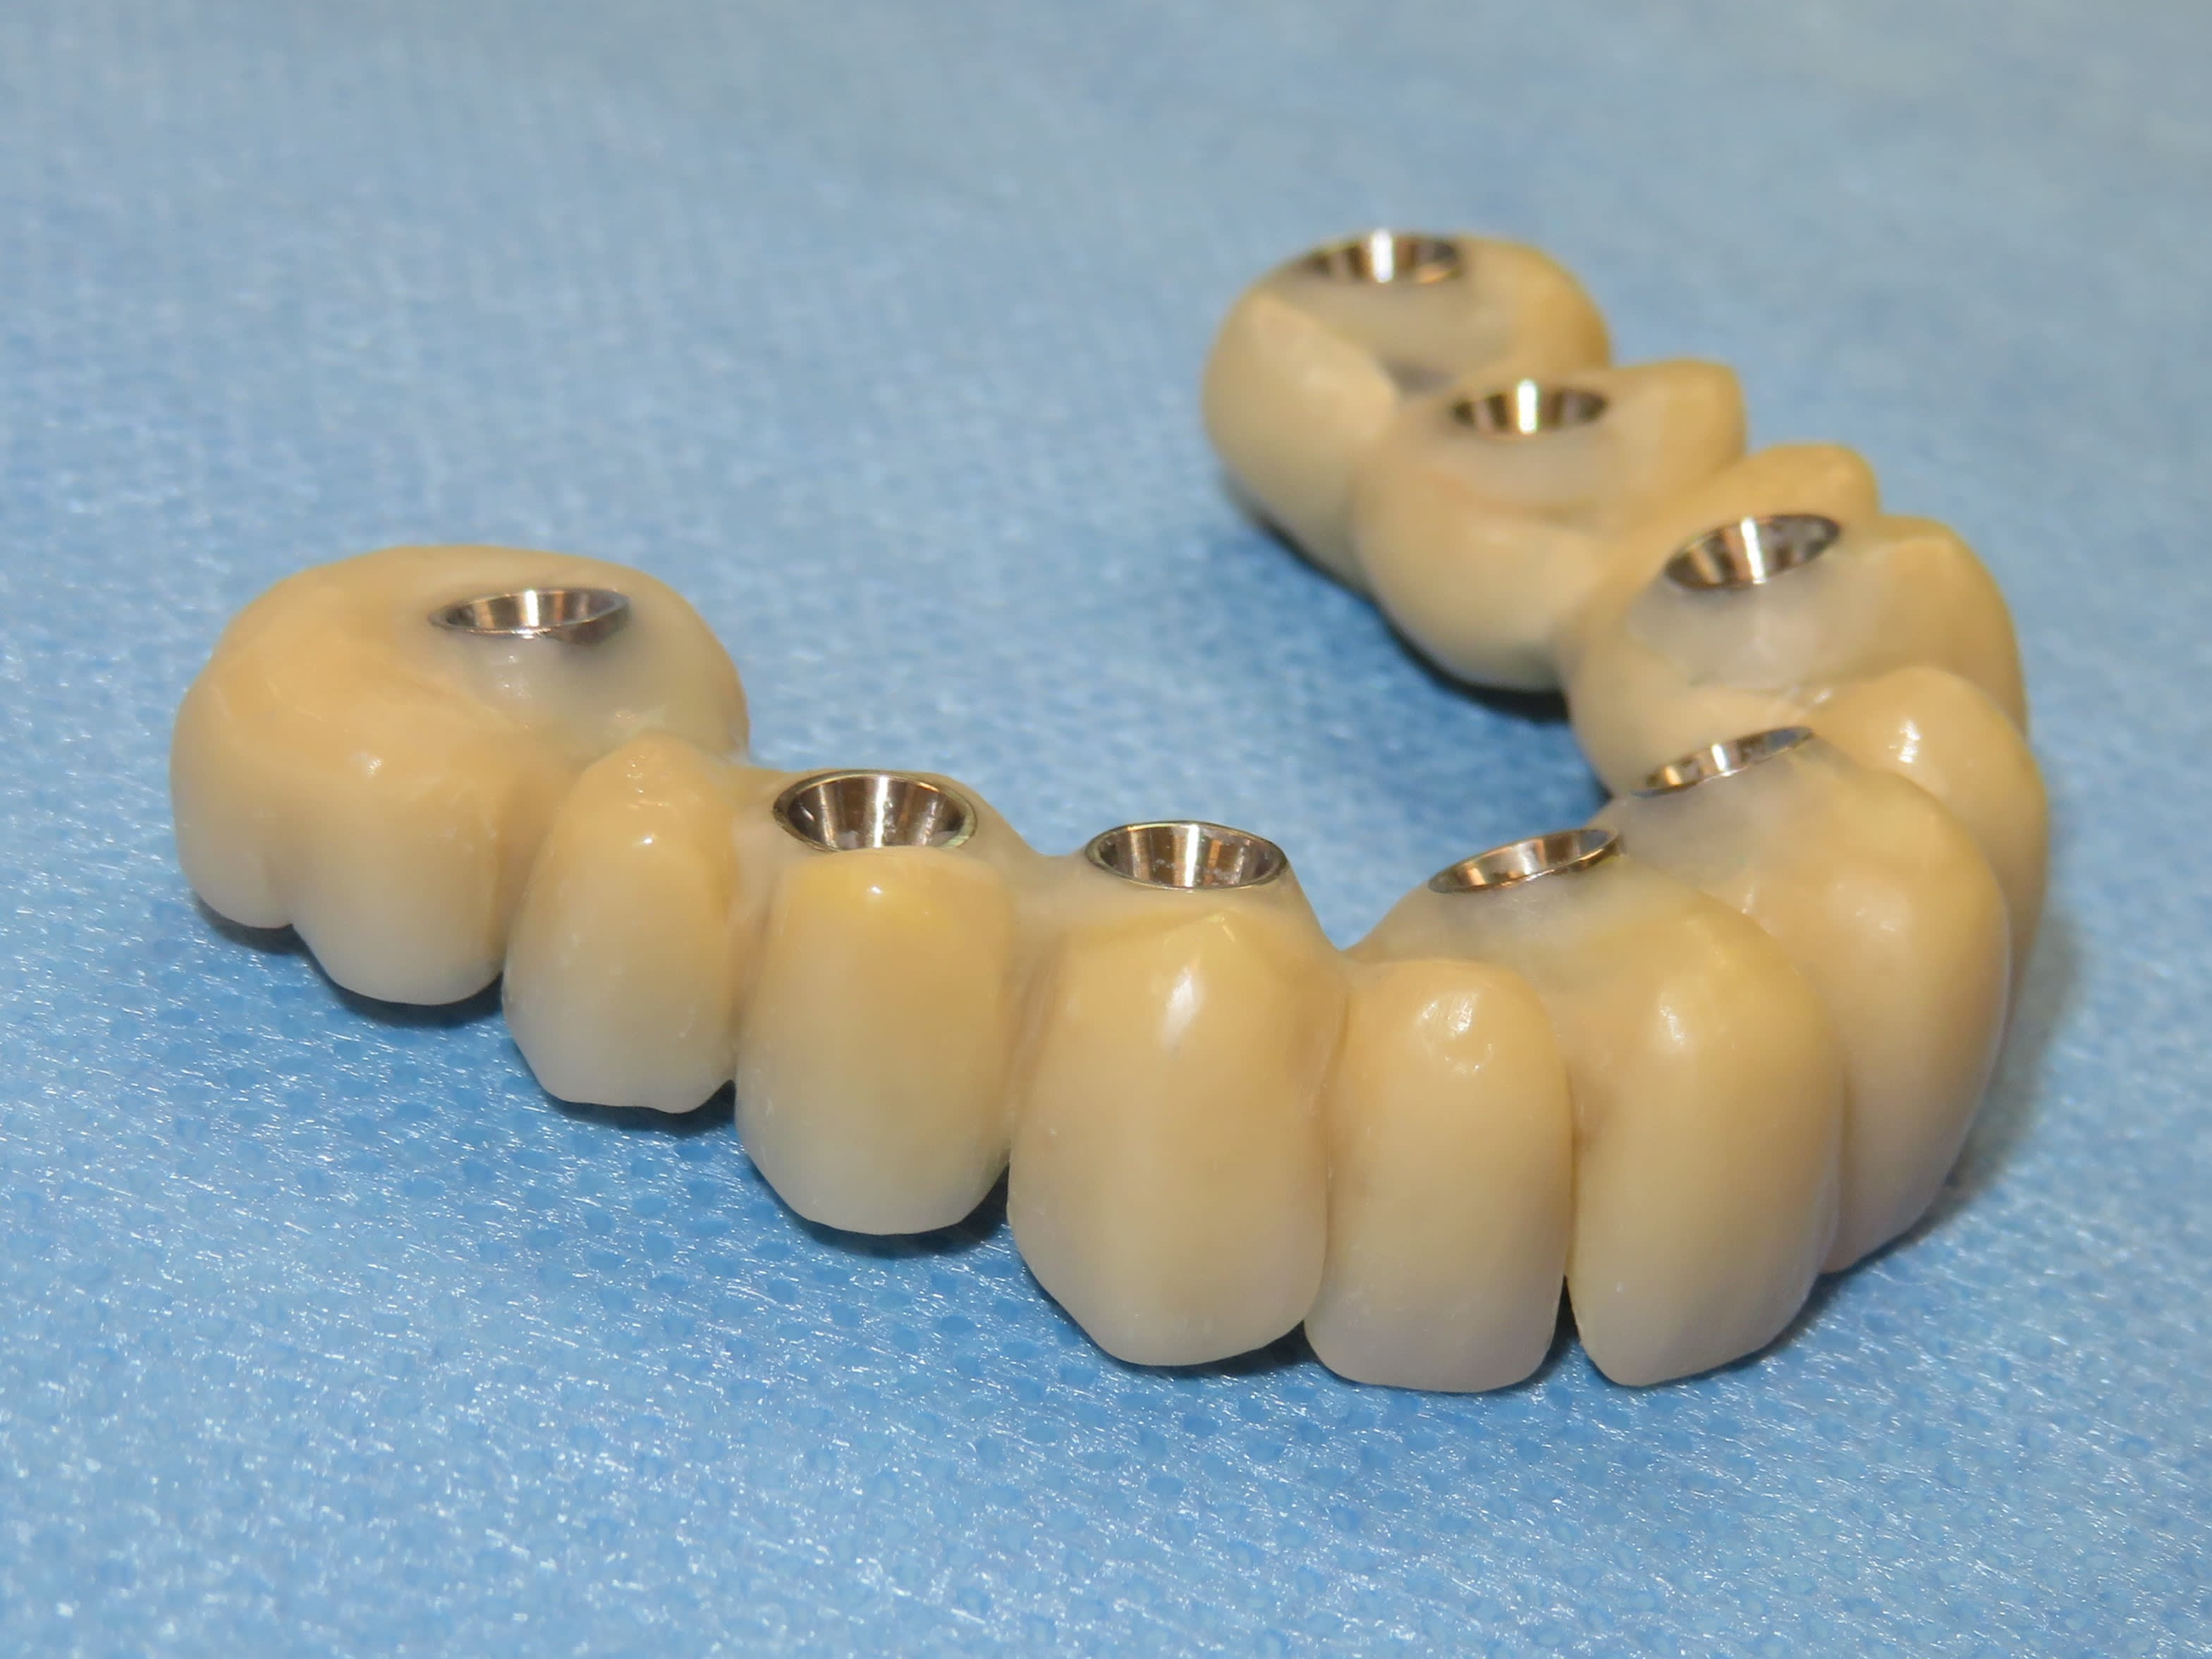

Autres cas de Dimitri : Quad zygo guidé, bridge full zircone tibase collé à l’avance.

Avec la zircone , le moindre défaut de passivité et le bridge est en deux …

Cela fait plus de deux ans qu’il utilise ce protocole.

Je crois que la, il n’y a plus de doute . Full zircone avec rosenscrew, pas de tibase .